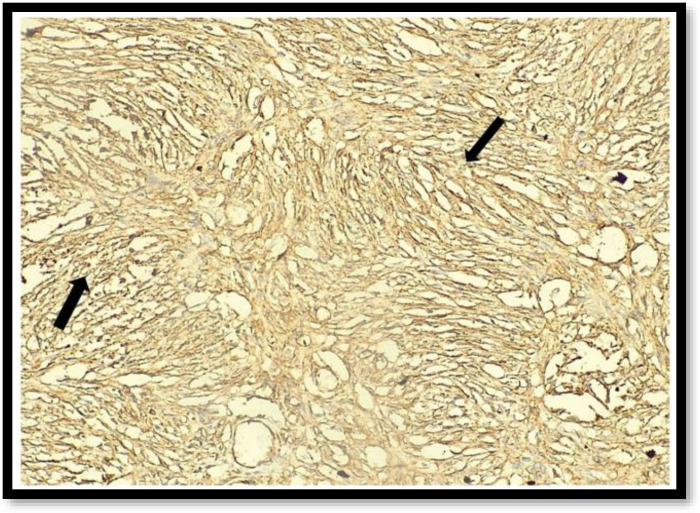

Objective: Dermatofibrosarcoma protuberans (DFSP) of the vulva is an uncommon soft tissue tumor with fewer than 60 cases reported previously. Distant metastasis is rare with a high propensity for local invasion. Surgical management is the gold standard with adequate margin excision to prevent future recurrences. We report a case of vulvar DFSP requiring three resections to achieve primary clearance. To the best of our knowledge, this is the first case report from India. Case report : A 35-years-old female, presented with nodular vulvar mass for the third time arising from the upper part of right labia majora for the last year. She had a history of two similar episodes in the past for which excision was done and histopathology confirmed DFSP. The third wide local resection was performed with 3 cm margins and the margins were sent for intra-operative frozen section analysis, which was confirmed clear by the pathologist. The patient has been free of recurrence for two years. Conclusion: DFSP is a challenging condition presenting as a non-tender nodular mass characterized by local invasion and recurrence. Early diagnosis and appropriate management using wide local excision with accurate margin assessment can achieve optimal results and prevent future recurrences.